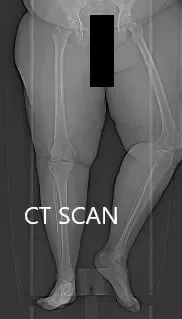

Topographic CT images of the weight-bearing Right and Left knee respectively.

A few weeks prior, a CT scan of the bilateral lower extremities was performed to obtain detailed data on the patient’s unique anatomy and biomechanics of the knees. A preoperative plan was formed to guide the surgeon in bone cuts and offsets. Disposable instruments were custom made for the patient. Unique customized implants were made to match the patients cut surface of the knee.